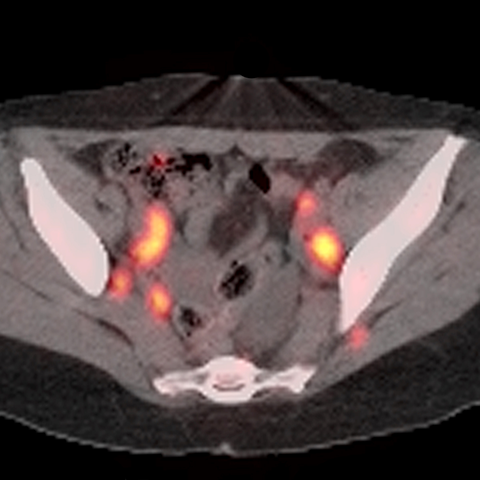

40 year old male presents with lymphadenopathy and unexpected weight loss [3 of 4]